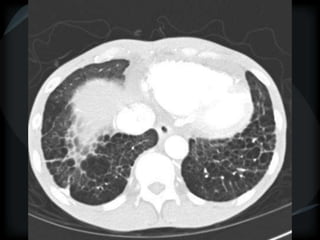

Reticular Pattern - NSIP

inflammation and fibrosis

 Predominantly basilar

 Significant ground glass

 Subpleural sparing low sensitivity, high specificity

 No honeycombing, some cystic change

 Traction Bronchiectasis

Diagnostic accuracy 50%

 Cellular NSIP

 Fibrotic NSIP

 Associated with CVD

 Undifferentiated CVD – T. King

NSIP- cellular

NSIP-fibrotic